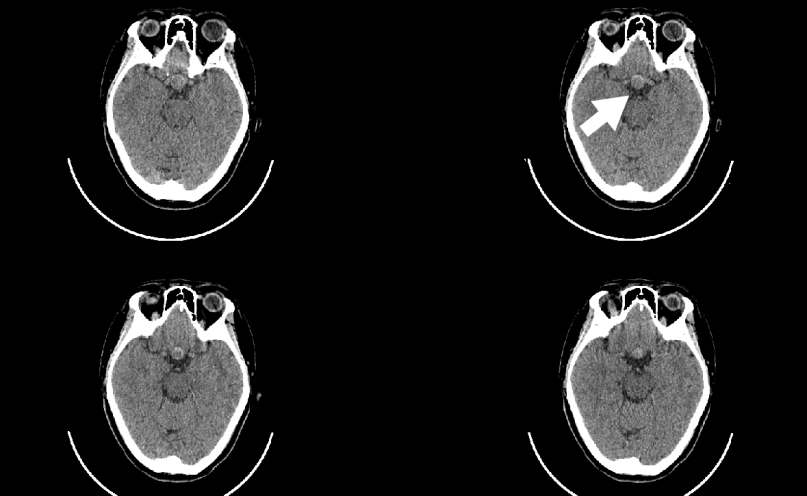

陳先生早晨起床時,突然感覺肢體無力,言語不清,站立、持物等活動受限。他被緊急送到醫(yī)院,急診ct檢查發(fā)現(xiàn)左側(cè)顳頂葉腦出血,并且疑似腫瘤出血。醫(yī)生進一步檢查發(fā)現(xiàn),患者顱內(nèi)巨大腫瘤并卒中(出血),情況十分危險,緊急開通綠色通道施行手術(shù)才保住了生命,病理診斷是膠質(zhì)瘤!